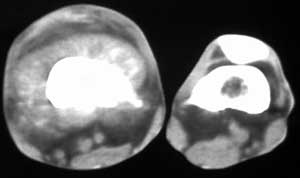

标题: CT4055:骨肉瘤?

男56涨疼5-6月

右股骨下端包绕股骨见巨大软组织肿块,密度部俊,周围见瘤骨,下端骨皮质侵蚀变薄,骨质周围无骨膜反应, 考虑右股骨软骨肉瘤。

右股骨下段周围软组织肿块伴钙化,相邻股骨骨皮质受累,考虑软组织来源恶性病变

右股骨下段骨肉瘤,软组织内瘤骨,软组织肿块。